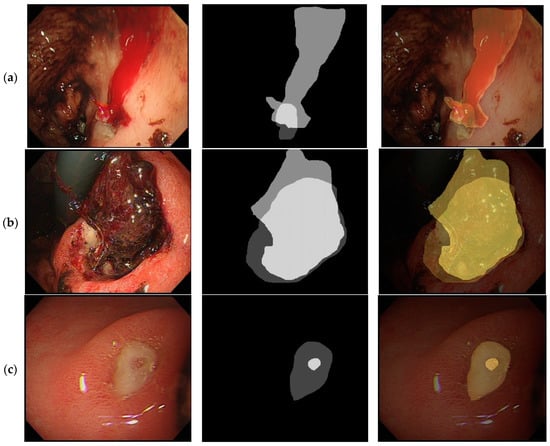

2.2. Process of Peptic Ulcer Image Segmentation